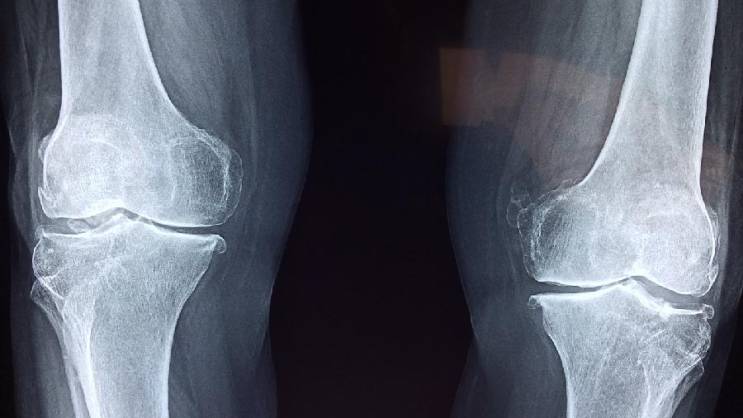

Foto: Ilustracija, Pixabay

Kosti često oslabe i postanu lomljive bez ikakvih simptoma, a toga postajemo svesni tek kada dođe do preloma.

„Pošto je slabljenje kostiju često neotkriveno, prvi način na koji ljudi mogu da saznaju koliko su im kosti zdrave je skeniranje gustine kostiju, ili DEKSA skeniranje, koje se preporučuje za svaku ženu stariju od 65 godina, mlađe žene u riziku od razvoja osteoporoze i muškarce starije od 70 godina“, rekao je za „The Parade“ dr Heter L. Hoflih.

„Nažalost, osteoporoza i osteopenija su često tiha stanja. Većina ljudi ne oseća ništa u svojim kostima dok ne dođe do preloma“, upozorila je ona.

Međutim, prema riječima dr Fišman, postoji rani znak da kosti slabe, a to je skupljanje.